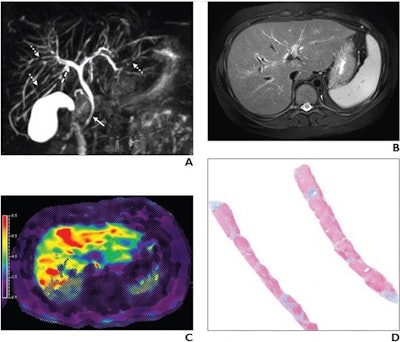

7-year-old boy with autoimmune sclerosing cholangitis and METAVIR stage 3 fibrosis on liver biopsy. (A) Coronal maximum intensity projection MR cholangiopancreatography (MRCP) image shows multiple intrahepatic strictures (dotted arrows), narrowing of common bile duct (solid arrow), and mild dilation of central biliary tree (dashed arrow). (B) Axial T2-weighted fast spin echo MR image with fat suppression shows enlarged liver with increased T2-weighted signal intensity. (C) Axial MR elastogram image shows heterogeneous appearance of liver with abnormal stiffening (mean liver stiffness, 6.55 kPa). (D) Tissue specimen (Mason trichrome stain; digital scan at 1x magnification) from percutaneous liver biopsy shows abnormally increased fibrosis (blue). Image and caption courtesy of the AJR.